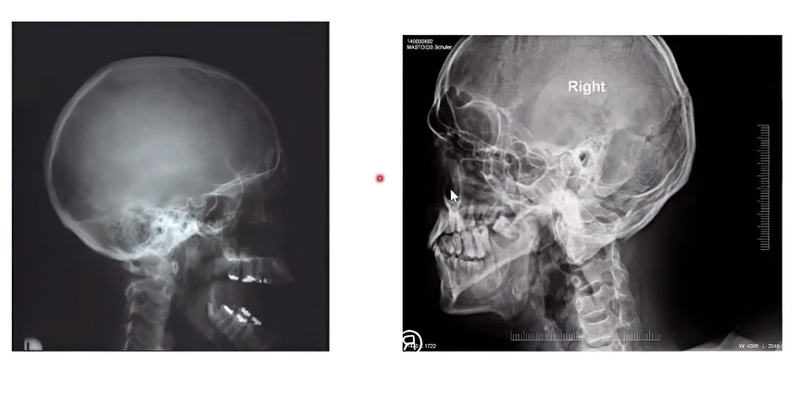

Chụp X quang tư thế schuller là kỹ thuật chụp X quang giúp thể hiện rõ nhất hình ảnh khớp thái dương hàm, hai bên vách của khe sào bào và sào đạo thượng nhĩ. Thông qua hình ảnh chụp X quang thu được, các bác sĩ có thể phán đoán nguyên nhân, chẩn đoán bệnh chính xác và đưa ra hướng điều trị bệnh phù hợp.

Sau khi chụp X quang schuller, bác sĩ quan sát phim X quang thấy rõ được các thông bào và cách ngăn của chúng chứng tỏ kết quả bình thường. Nếu phim chụp thể hiện các đặc điểm dưới đây, bệnh nhân có nguy cơ đã xuất hiện các bệnh lý ở khớp thái dương hàm hay xoang xương chũm: